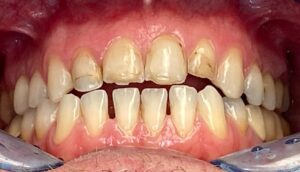

La teoria trova la sua conferma definitiva nella pratica quotidiana del nostro laboratorio. Negli ultimi mesi, abbiamo documentato numerosi casi in cui la Flow Injection Technique ha risolto sfide estetiche complesse con una naturalezza sorprendente.

Dalla chiusura dei diastemi al ripristino di intere arcate usurate, i casi trattati da Dentalstyle dimostrano che è possibile coniugare un approccio ultra-conservativo con un’estetica di altissimo livello. Vedere il paziente sorridere con sicurezza, sapendo che i suoi denti sani sono rimasti intatti, è la soddisfazione più grande per il clinico e per noi tecnici.